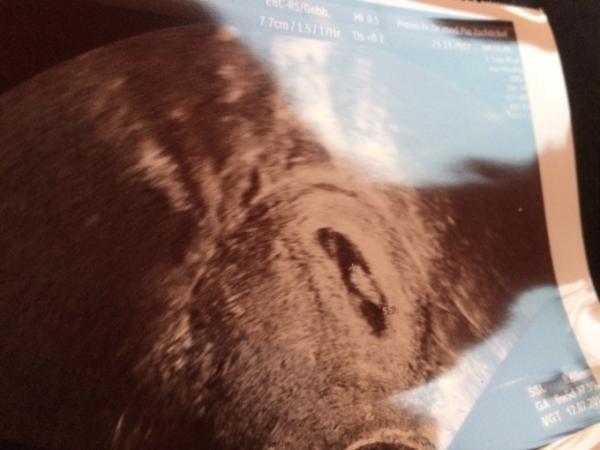

Hallo ihr Lieben, ich war ja heute Morgen beim FA. Es ist alles wunderbar. Meine kleine Bohne ist ca. 1 cm groß und auf den Tag genau gewachsen. Es wird voraussichtlich am 12.07.18 auf die Welt kommen wollen das Herz hat heute schon schön geschlagen. Habe auch meinen Mutterpass bekommen. Am 14.12.17 darf ich wieder hin. So jetzt entspann ich mich schön und leg mich zurück.

Bild zu Meine kleine Bohne - Forum für Juli - Mamis